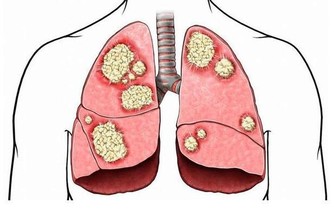

3、保護肺部,遠離肺癌。

有研究顯示,30歲以前戒菸能使肺癌的風險降低90%,戒菸5年後,

由於吸煙所致的口腔和食管腫瘤風險也會降低一半。

多吃堅果。堅果富含元素硒,尤其是開心果。

開心果中的維E也可以保護肺部,降低患肺癌的風險。